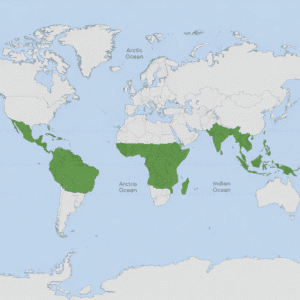

Parasites in Humans: Symptoms, Causes, Treatment, and Prevention

Parasitic infections are more common than are thought, with as many as…